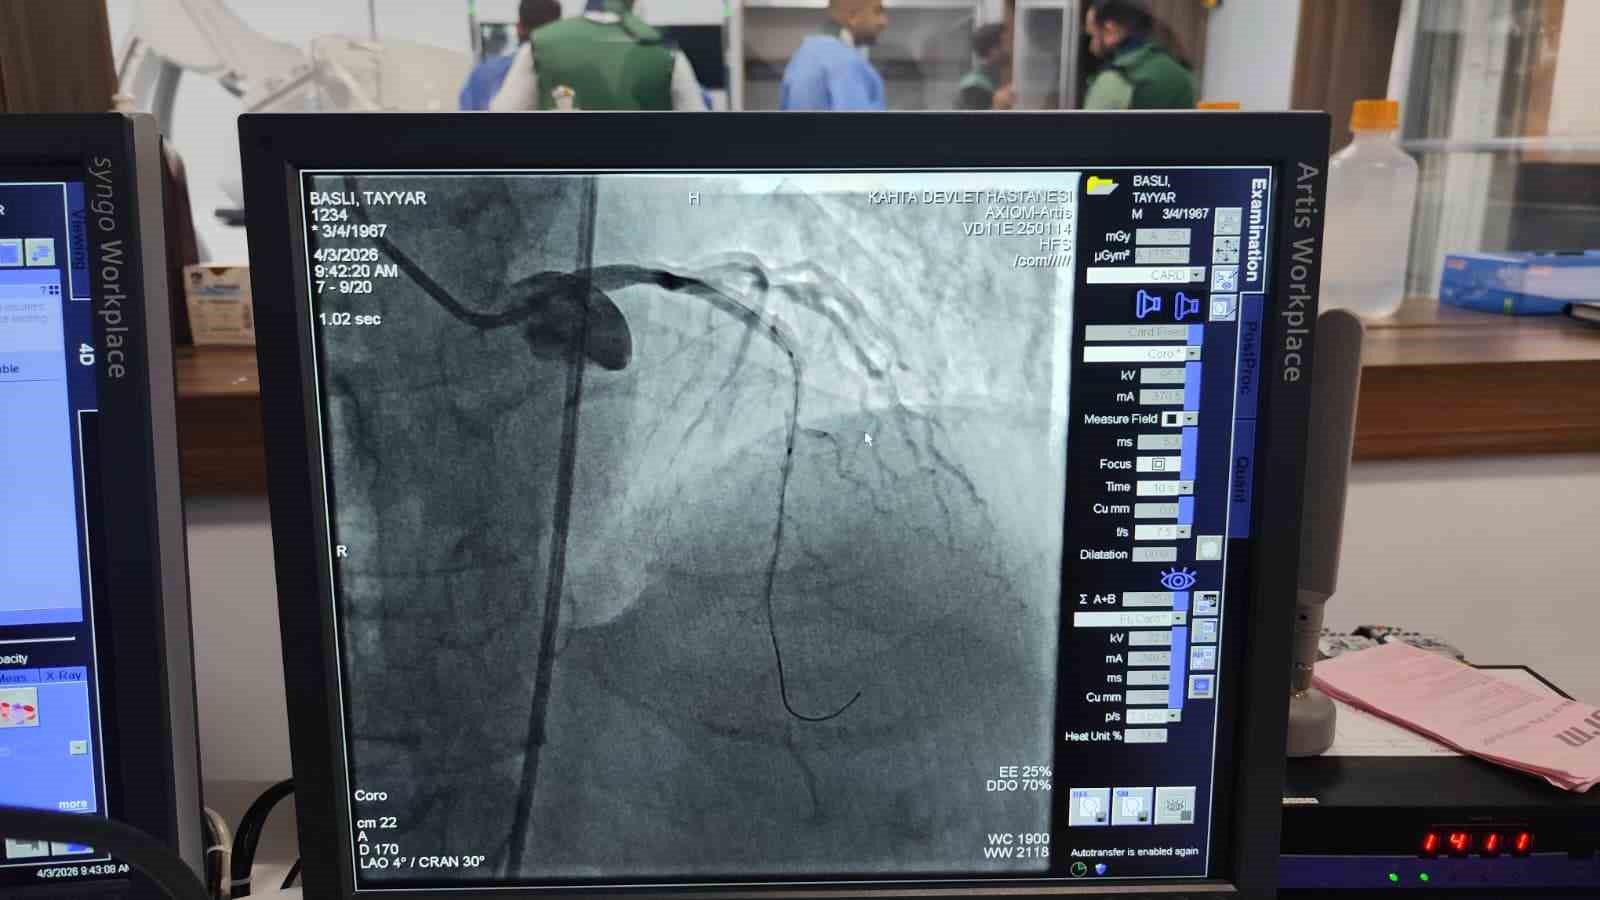

Adıyaman’ın Kâhta Devlet Hastanesi bünyesinde kurulan anjiyo ünitesinde ilk hasta da başarıyla tedavi edildi.

Kalp ve damar hastalıklarının tanı ve tedavisinde önemli bir eksikliği gidermesi hedeflenen anjiyo ünitesi, hizmete alınmasının hemen ardından ilk vakasını kabul etti. Kalp krizi şüphesiyle Kâhta Devlet Hastanesi Acil Servisi’ne başvuran hasta, yapılan ilk müdahalenin ardından vakit kaybetmeden anjiyo ünitesine alındı. Burada gerçekleştirilen operasyonla hastanın kapalı olan iki damarına stent takıldı. Müdahalenin ardından hastanın genel sağlık durumunun iyi olduğu öğrenildi.

Kâhta Devlet Hastanesi Başhekimi Dr. Mustafa Akel, "Hastanemizden 45 km mesafede ikamet eden 59 yaşındaki hastamız, göğüs ağrısı şikâyeti ile hastanemize başvurmuştur. Yapılan tetkiklerde kalp krizi geçirdiği tespit edildi ve acil bir şekilde yeni açmış olduğumuz anjio merkezimize hastayı aldık. Yapılan görüntülemede kalbinin ön damarı olan LAD mid bölgesi total tıkalı tespit edildi. Hastamızın kalbinin ön damarına iki adet stent takarak tam açıklık sağlandı. Hastamızın genel durumu iyi olup yoğun bakıma takip amacıyla alındı" dedi.